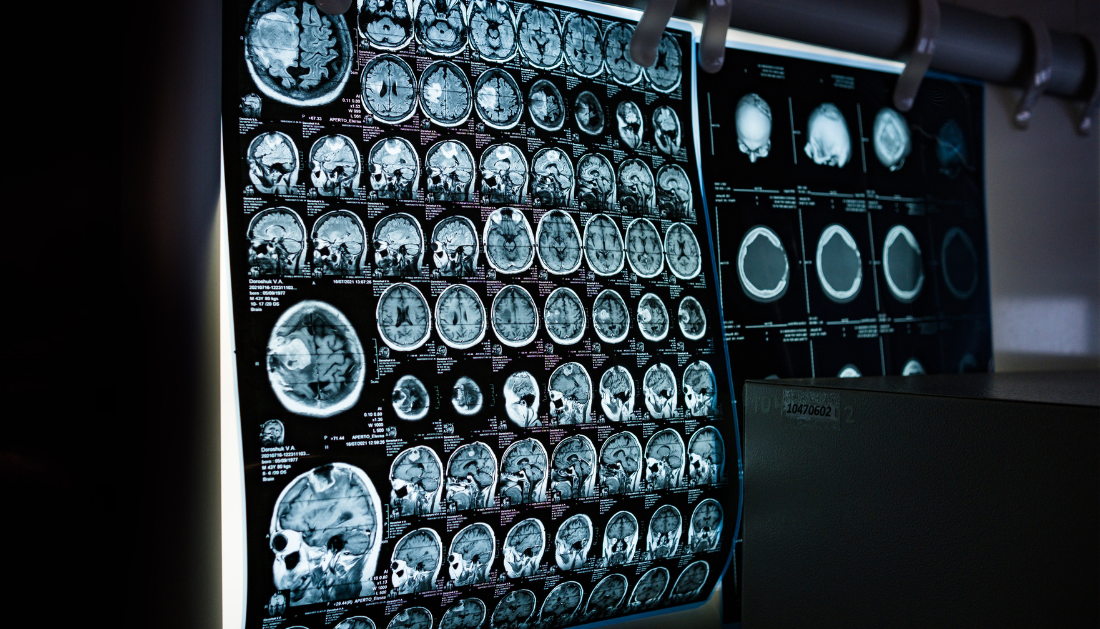

A recent clinical trial published in Brain Communications challenges a long-held assumption in stroke rehabilitation, that increasing therapy intensity early after stroke leads to better outcomes. The ESPRESSo trial, led by researchers at the University of Auckland, found that high-intensity therapy initiated within two weeks of stroke did not significantly enhance hand and arm recovery compared to standard care.

The trial enrolled 64 stroke survivors and introduced high-repetition, high-intensity therapy over three weeks, adding 90 minutes of daily therapy to standard care. Patients were uniquely selected using a recovery biomarker, allowing a more targeted approach to rehabilitation.